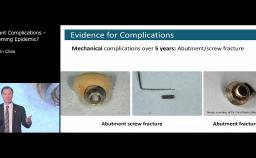

Treatment Outcomes and Continuing Care

Implant Complications – A Looming Epidemic?

Congress Lecture